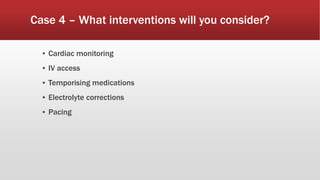

This document discusses various cases of collapse and syncope. It defines collapse as transient loss of consciousness with loss of postural tone and full recovery. Syncope is defined as loss of postural tone with or without loss of consciousness and full recovery. It then discusses the multiple potential causes of collapse and syncope including toxicological, cardiac conduction abnormalities, structural cardiac issues, autonomic dysfunction and more. It then goes through 9 case examples, discussing important questions to ask, potential tests and interventions for each case.